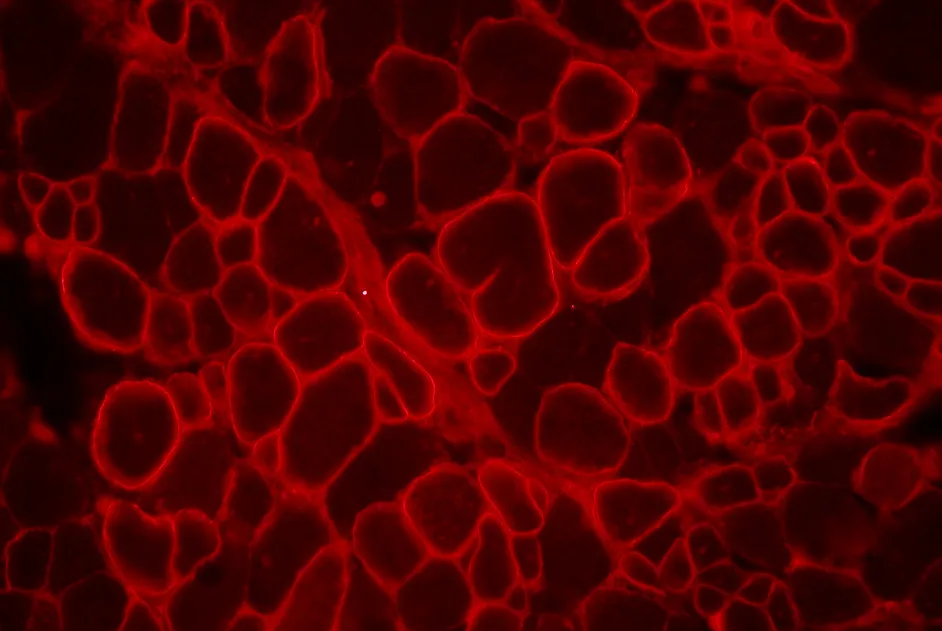

SMA : de l’importance de la protéine SMN dans les organes périphériques

Une nouvelle étude, soutenue par l’AFM-Téléthon, montre que la restauration par thérapie génique de SMN uniquement dans les motoneurones de souris n’est pas suffisante.